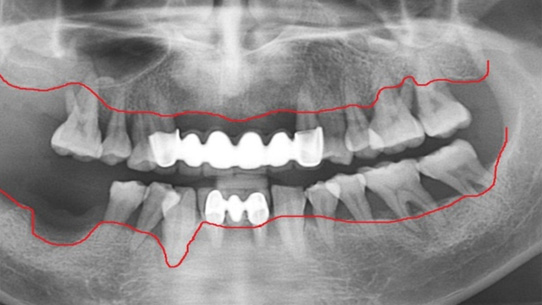

잇몸뼈가 녹아내려 임플란트 12개 진단을 받고 내원한 환자, 고운미소에서 치주치료를 시행한 결과 전치부 잇몸이 개선되어 발치 하지 않고

크라운으로 수복하였고, 어금니에 6개의 임플란트를 식립하였습니다.

잇몸 염증으로 치조골 손실이 많은 상태

잇몸건강이 회복된 앞니는 크라운으로 수복